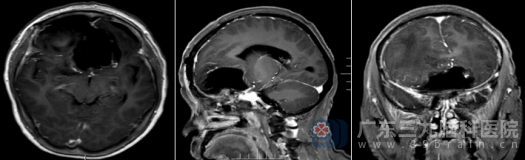

术后复查头颅MR显示“呈术后改变”,意味着肿瘤已被成功切除。病理报告带来了好消息:肿瘤为“脑膜皮细胞型脑膜瘤,CNS WHO 1级”,属于良性肿瘤,生长缓慢,预后良好。

王阿姨的恢复情况令人欣慰。经治疗王阿姨神志清醒,视力较术前有所好转,虽然嗅觉因神经长期受压、破坏,尚未恢复,但其他症状明显改善。